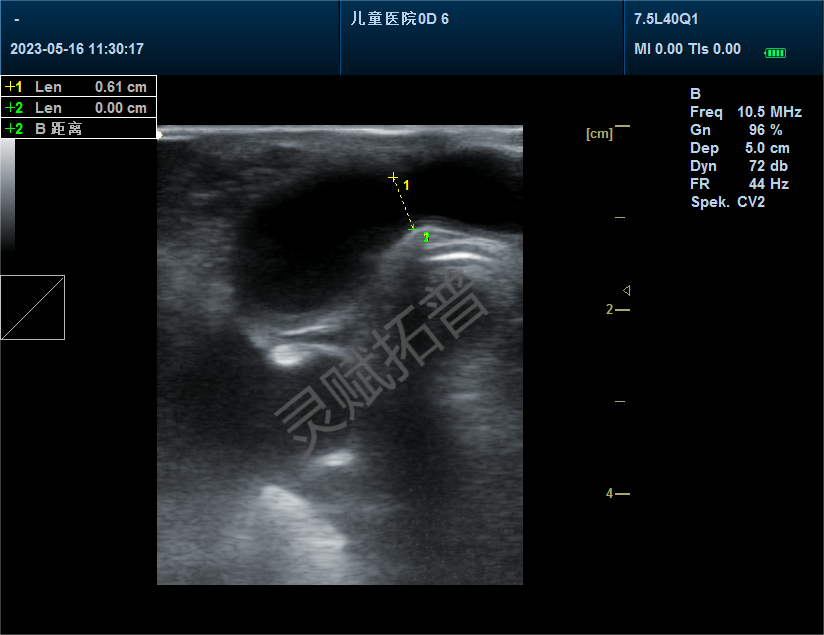

超声心动图显示室腔缩窄、心肌肥厚增大

手术后13周比格犬超声结果